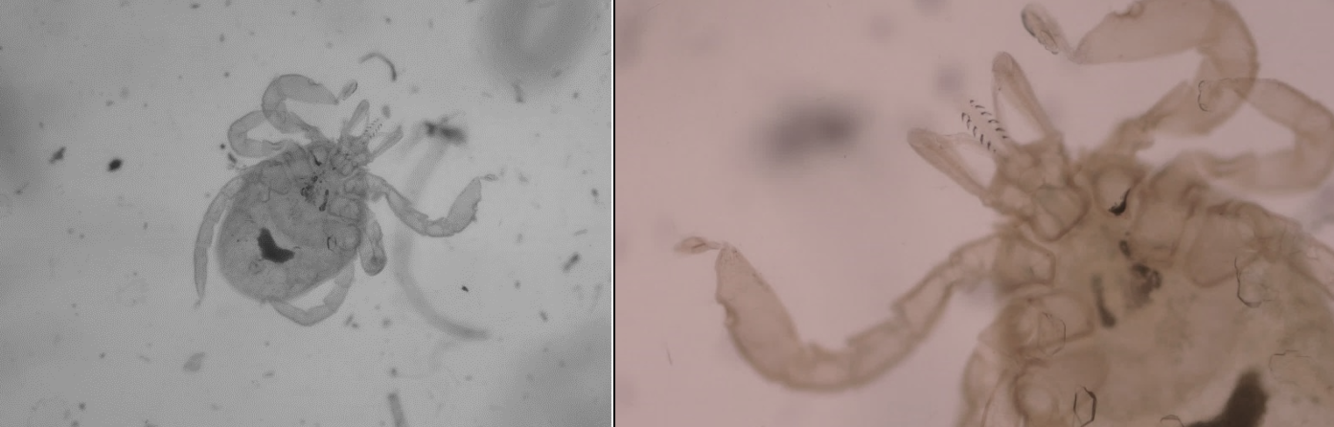

14

Q

identify this parasite

A

tick

15

ear mites (otodectes cynotis)